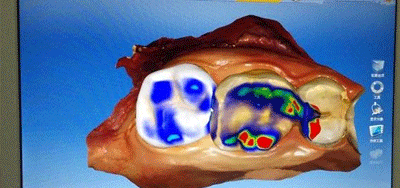

CAD/CAM全瓷嵌体个性化设计

光学取模

生物再造软件生成牙体形态

CAD/CAM 3D打印全瓷嵌体